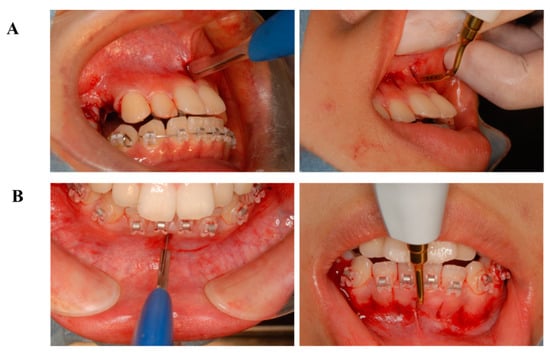

5. Accelerating Orthodontic Tooth Movement (AOTM) and Inflammation—Is Inflammation a Friend?

6.4. Treatment Progress